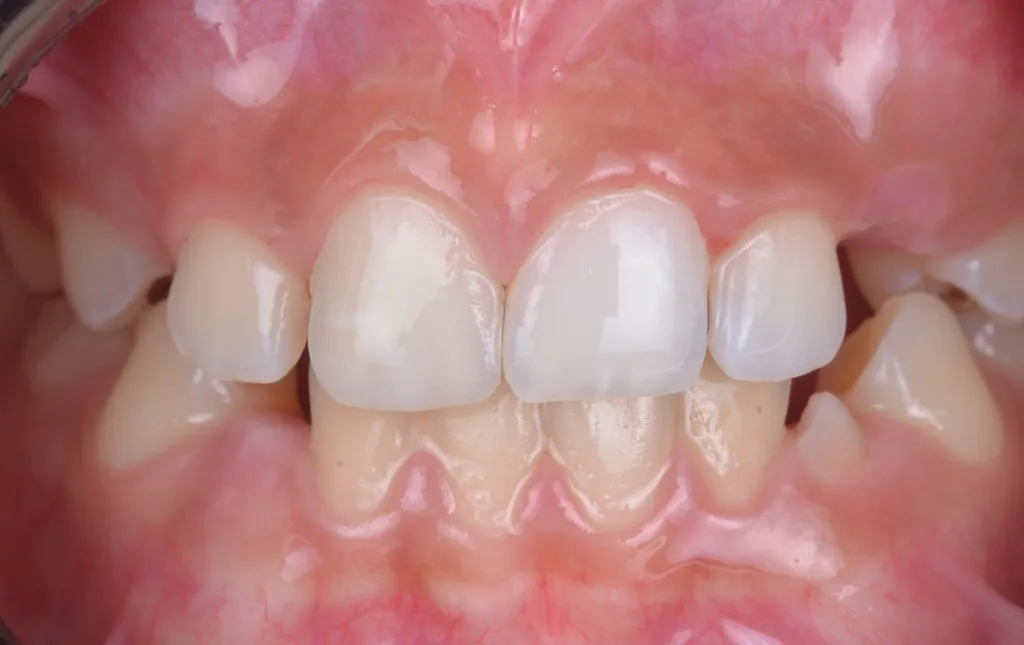

Um diesen Herausforderungen zu begegnen, wurden verschiedene modifizierte Behandlungsprotokolle entwickelt. Diese beinhalten unter anderem die Verlängerung der Infiltrationszeiten, das gezielte Abtragen der Oberflächenschicht (idealerweise als „selective surface removal“ unter Transilluminationskontrolle), um den Zugang des Infiltranten zum Läsionskörper zu ermöglichen, sowie eine Vorbehandlung mit oxidierenden Substanzen, um die Durchlässigkeit des Schmelzes für den Infiltranten zu steigern [17,18]. Darüber hinaus hat sich die optische Kontrolle der Infiltration mittels Transillumination als hilfreiches Instrument erwiesen, um den Infiltrationserfolg in Echtzeit besser beurteilen zu können und die Behandlung entsprechend anzupassen [17] (vgl. Fallbeispiel in Abb. 2).

![i) nach Abschluss der Behandlung und Aufbau der Inzisalkante mit Komposit. Der gezeigte Fall wurde im Rahmen einer bereits veröffentlichten Studie behandelt [17].](https://dentalwelt.spitta.de/wp-content/uploads/2026/04/Abb2I-1024x645.webp)